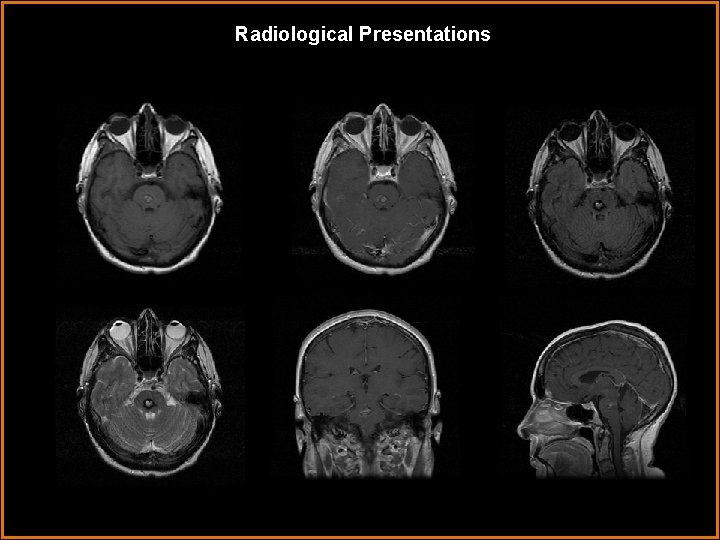

Radiological Presentations

Findings and Differentials Findings: Axial T 1 and T 2 and saggital T 1 MR images demonstrate a lesion with heterogeneous signal on both T 1 and T 2, centered in the mid pons. This has a rim of low signal on T 2.

Discussion • Cavernous Hemangioma: Cavernous hemangiomas are considered congenital vascular hamartomas consisting of a sinusoidal collection of blood vessels without interspersed normal brain. They may cause seizures or other neurologic symptoms, but are often asymptomatic. They may also hemorrhage. They can occur anywhere, including the spine. They often have calcifications, enhance, and usually demonstrate blood products of varying ages. On MR, classically a hemosiderin rim is seen with low T 2 signal which completely surrounds the collection. Often these lesions are angiographically occult. This fits well with our patient's imaging. The location doesn't help us much, but the heterogenous signal, representing blood products of varying ages, and the complete rim of hemosiderin are virtually diagnostic.

Diagnosis Cavernous Hemangioma